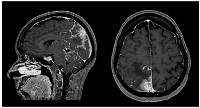

Figure 1

CE MRI at BM and LMC initial moment of diagnosis.

Heterogeneous space-occupying lesion (right posterior parietal-parasagittal cortico-subcortical area), with vasogenic edema and sulcal effacement, compatible with a BM lesion, along with pachymeningeal carcinomatosis (right next to the first described BM).

Sixteen months later (1.3 years), the patient was admitted to the emergency department with severe right headache (only mild response to pain medication and presence of other red flags: vomiting, night awakening, neurological deficits - visual deficits, facial paresthesias, dizziness; vertigo and decreased left upper limb muscular strength). Cranioencephalic computed tomography (CE-CT) showed a heterogeneous space-occupying lesion, in the right posterior parietal-parasagittal cortico-subcortical area, with vasogenic edema and sulcal effacement, compatible with a new BM lesion. Cranioencephalic magnetic resonance imaging (CE-MRI) confirmed the lesion genesis, showing new pachymeningeal carcinomatosis (right next to the lesion) and disseminated leptomeningeal carcinomatosis (LMC) (extended to cerebellar fissures, midbrain and brachiocephalic bridge, involving the cranial nerves emergence as well) (Figure 1). An important mass effect was present, compressing and occluding the right vertebral artery V4 terminal segment. Neuraxis MRI confirmed disseminated LMC in all neuraxis (extension to the conus medullaris limit) (Figure 2). Lumbar puncture showed a turbid cerebrospinal fluid (CSF), with cytology demonstrating small, scattered lymphocytes, large epithelial cells exhibiting irregular, hyperchromatic nuclei, and the presence of the ‘cell-in-cell’ phenomenon. The fluid was histologically confirmed as central nervous system (CNS) metastasis of HER2 positive BC. Re-staging showed neither local nor distant disease.